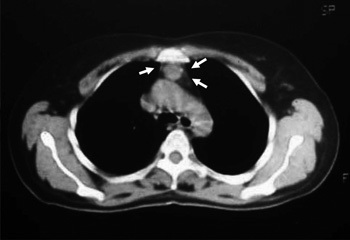

Scanner thoracique réalisé dans le bilan d’une myasthénie: que voit-on?

Thymus hyperplasique résiduel.